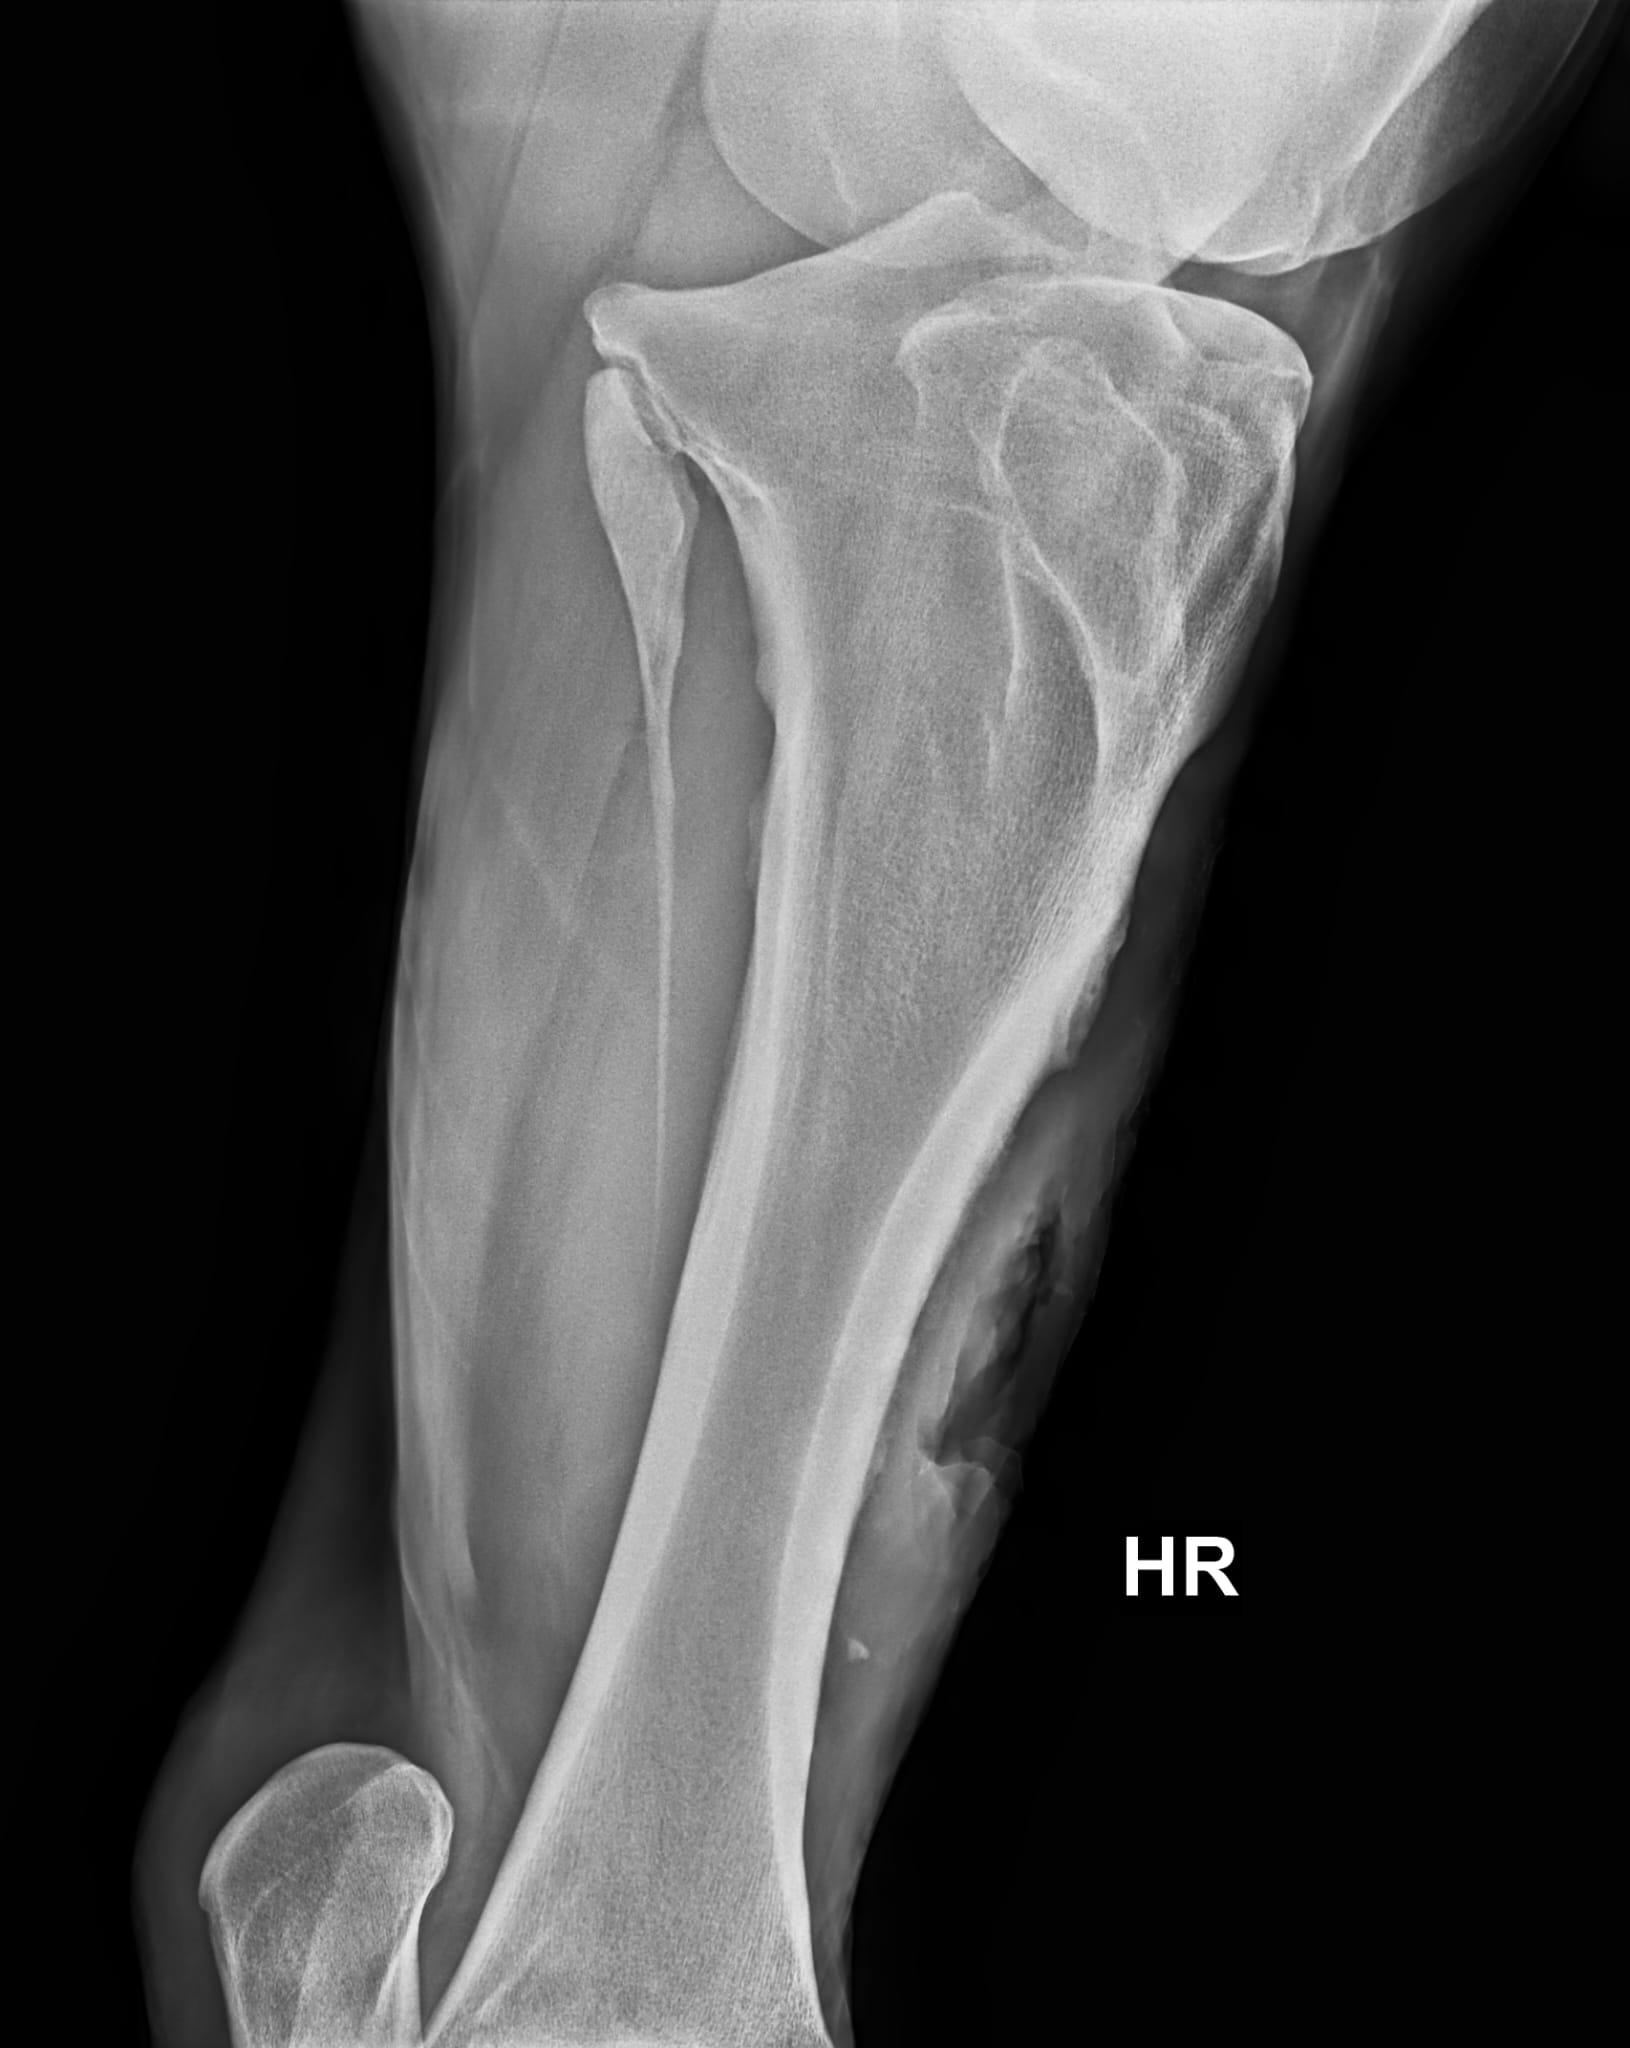

Allein die Befreiung des panischen Pferdes aus seiner misslichen Lage erforderte viel Einfühlungsvermögen. Was uns dann aber erwartete, stellte uns doch vor eine schwierig zu lösende Aufgabe: Neben der stark blutenden Wunde mit großem Hautverlust erbrachte die röntgenologische Untersuchung, dass der Knochen des Unterschenkels auf einer größeren Länge auch noch angebrochen war.

Was ein Dilemma! Eigentlich hätte die schwer zugängliche, deutlich kontaminierte Wunde in Vollnarkose versorgt werden müssen, der Schockzustand von „Hans“ und der angebrochene Knochen schlossen dies aber strikt aus, da die große Gefahr bestand, dass der Knochen beim Aufstehen nach der Narkose vollständig brechen könnte.

Aufgrund des angebrochenen Unterschenkelknochens wurde das Bein mit einem dicken Polsterverband unter Einbeziehung von stabilisierenden Gipsbinden so gut wie möglich geschient. Die erste Zeit verbrachte „Hans“ natürlich auf unserer Intensivstation, damit wir ihn 24 h überwachen und medizinisch versorgen konnten. Er kämpfte wie ein Löwe und allen Befürchtungen zum Trotz verheilte die Wunde zwar langsam, aber ohne gefährliche Wundinfektion und der angebrochene Knochen wuchs wieder glatt zusammen. Was ein Glück!